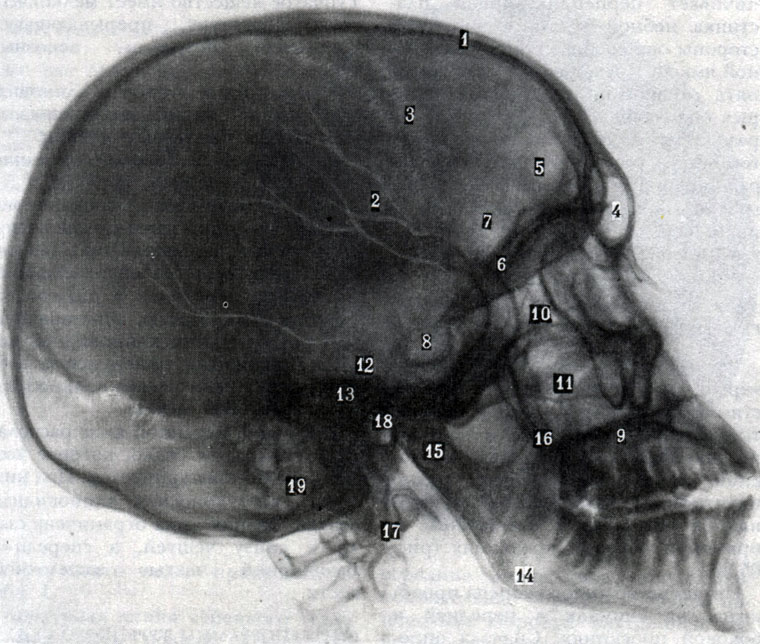

Анатомия детского черепа: Рентгеновские снимки и описание